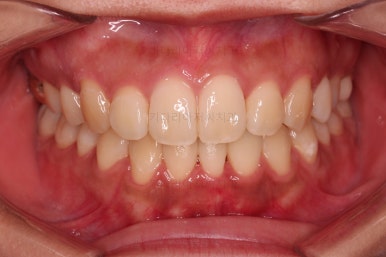

초진 시 입안의 모습입니다.

그냥 봐도 뭔가 애매함이 있죠?

중앙선이 맞지 않고, 교합이 떠보이는 양상이네요.

윗니는 좌측 작은 어금니가 한 개 모자랐고 아랫니는 앞니 하나가 모자라네요.

그런데 앞니는 아랫니가 1개 모자란 채로 교합이 맞춰져서 윗니가 하나 부족한 채로 애매한 상태였어요.